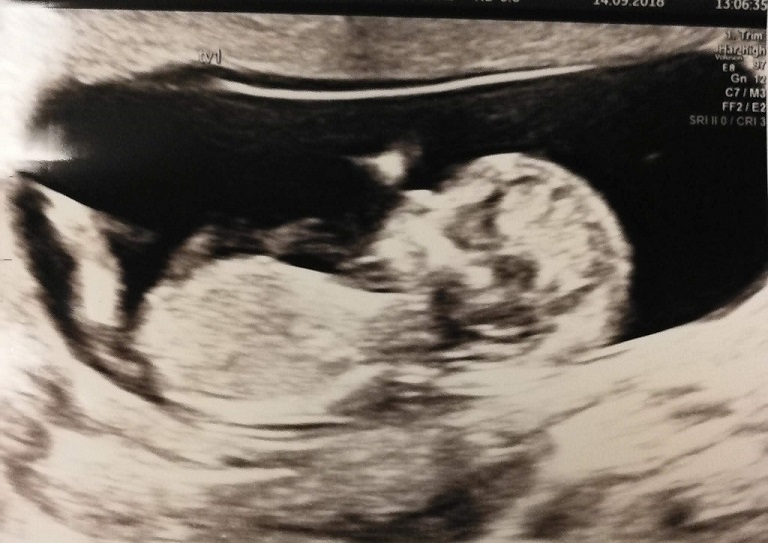

Anybody want to make some nub guesses? :) 12+5 with identical twins. Is it too early? Would love to hear your guesses :)

No clues in the first pic but all girl in the second. Congrats!!:happy:

cant see a nub in the first one but the second does indeed look girly :P congratulations!!! xo